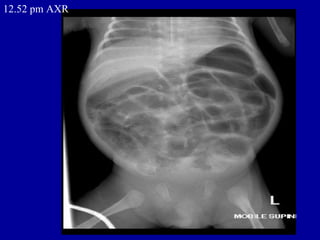

12.52 pm AXR

1.44 am

•   ORIGINAL REPORT

•   HISTORY

•   NEC, septic shock on CPAP, IA and IV lines.

•   REPORT

•   AXR - SUPINE AP

•   Compared with AXR taken 10 hours earlier.

•   The nasogastric tube is now seen projected over the left hypochondrium. There is

•   interval worsening of the gaseously distended intestinal loops. Faecal matter is

•   again seen in the proximal colon. No air or faecal matter seen in the pelvic cavity.

•   There is free extraluminal air within the peritoneal cavity, outlining the liver.

•   Rigler's sign is noted, consistent with intestinal perforation.